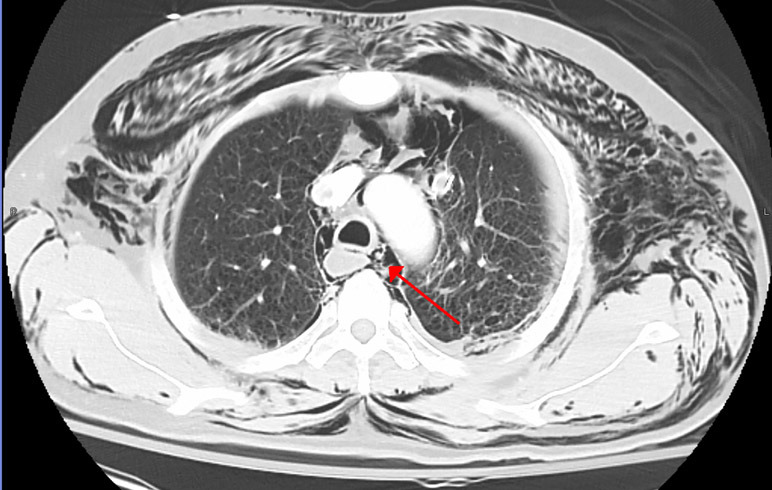

原发性自发性纵隔气胸是一种罕见的、通常是良性的、自限性的疾病,由纵隔内的空气所决定。然而,如何正确区分原发性自发性纵膈气胸和继发性气胸,尤其是食管穿孔,仍然是一项诊断难题。对于如何平衡完成全面但又不过分侵入性和昂贵的诊断工作,存在着很大的争议。本临床综述旨在收集来自病例系列和回顾性队列研究的有关自发性气胸治疗的有限数据,并根据临床病史提出分层评估算法和治疗方案。具体了解患者是否伴有咳嗽或用力呕吐对于阐明病因和指导气胸的治疗至关重要。对于出现剧烈呕吐或反胃的患者,应高度怀疑继发性气胸的病因,特别是食管穿孔。然而,特别是对于儿童患者,并不是每个病例都需要进行积极的诊断检查。在排除了其他导致气胸的病因后,自发性气胸通常可以通过对症治疗来解决,而无需积极使用抗生素或限制饮食。也可根据具体情况尽量缩短住院时间。总的来说,自发性气胸很少复发,因此只需对复发风险最高的患者进行门诊随访即可。

Primary spontaneous pneumomediastinum is a rare, often benign and self-limited condition defined by air within the mediastinum. However, correctly distinguishing primary spontaneous pneumomediastinum from secondary causes, especially esophageal perforation, remains a diagnostic challenge. There is significant debate regarding the balance of completing a thorough but not overly invasive and costly diagnostic workup. This clinical review aims to gather the limited data regarding spontaneous pneumomediastinum management from case series and retrospective cohort studies, and presents an evaluation algorithm and treatment plan stratified by clinical history. Understanding specifically if the patient presents with coughing versus forceful vomiting is critical to help elucidate the etiology and guide management of pneumomediastinum. Patients who present with forceful vomiting or retching should be considered with higher degree of suspicion for secondary causes of pneumomediastinum, specifically esophageal perforation. However, especially in children, aggressive diagnostic workup is not warranted in every case. After ruling out other etiologies of pneumomediastinum, spontaneous pneumomediastinum can be commonly treated with symptomatic management without the aggressive use of antibiotics or diet restriction. Hospital length of stay may also be minimized on a case-by-case basis. Overall, recurrence of spontaneous pneumomediastinum is rare and outpatient follow up may be safely limited to those at highest risk of recurrence.